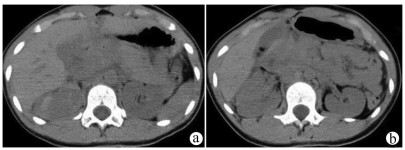

A preliminary study on percutaneous transhepatic drainage combined with sequential percutaneous nephroscopy in treatment of refractory liver abscess

Changhu DUAN, Xiaochen LIU, Jianlong DING, Jianfeng DUAN, Xirong ZHAO, Fan YANG, Ling WU, Lifei ZHAO, Sheng TAI

2021, 37(11): 2622-2625. DOI: 10.3969/j.issn.1001-5256.2021.11.026

Abstract(1082) HTML (221) PDF (2925KB)(64)

Abstract:

Objective  To investigate the clinical effect of percutaneous transhepatic drainage combined with sequential percutaneous nephroscopy for necrosectomy and drainage in the treatment of refractory liver abscess after transcatheter arterial embolization (TACE).  Methods  A retrospective analysis was performed for three patients with refractory liver abscess after TACE in The Affiliated 3201 Hospital of Xi'an Jiaotong University School of Medicine from January 2018 to December 2020, and among the three patients, one had the formation of liver abscess after TACE for hepatic metastases after pancreaticoduodenectomy, one had liver abscess after repeated TACE for massive hepatocellular carcinoma, and one had secondary liver abscess after TACE for traumatic hepatic rupture. All three patients received percutaneous transhepatic drainage and sequential percutaneous nephroscopy for the treatment of refractory liver abscess, and their specific treatment process was summarized.  Results  All three patients were diagnosed with refractory liver abscess based on CT, routine blood test, procalcitonin, blood culture, and clinical manifestation. Percutaneous transhepatic catheterization under the guidance of conventional ultrasonography or CT and effective antibiotics had an unsatisfactory therapeutic effect, and after sequential percutaneous nephroscopy was performed for necrosectomy and drainage, liver abscess was cured and the patients had good prognosis.  Conclusion  For refractory liver abscess after TACE, when routine puncture treatment has an unsatisfactory therapeutic effect or a patient cannot tolerate surgical operation, percutaneous transhepatic drainage combined with sequential percutaneous nephroscopy is safe and effective in the treatment of refractory liver abscess.